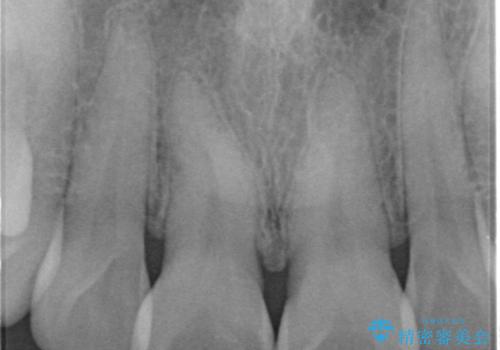

転んで前歯が折れた 色合いの難しい歯のセラミック修復

- 転倒し前歯を地面に強打して折れたとのことで来院。

幸い神経は生きており、セラミックでかぶせることになりました。

まず保険治療でコンポジットレジン修復を行い、神経の状態を確認した後、クラウンによる修復を行いました。

将来神経が失活する可能性もありますので経過観察する必要があります。